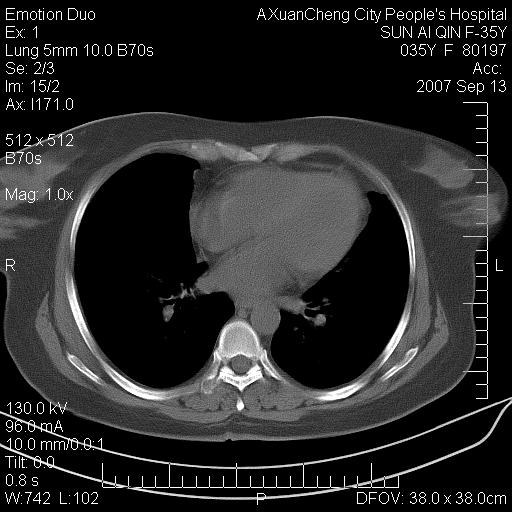

以下是引用天南地北在2007-9-13 13:43:00的发言:[br]考虑双肺、肺门侵润

以下是引用ydx_74在2007-9-13 15:42:00的发言:[br]仅看片,考虑右上肺癌并双肺转移,结合病史,考虑肺门、肺内淋巴侵润

以下是引用同在2007-9-13 15:08:00的发言:[br]支持肺门及双肺侵润.